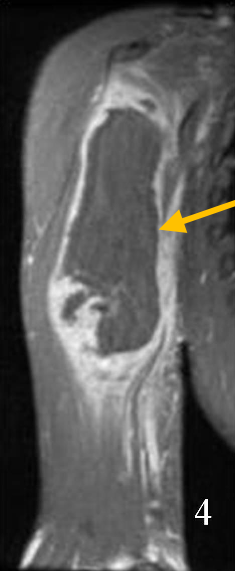

Radiographic imaging is used to help form a diagnosis. These include X-Ray, MRI, CT and Bone Scans

An example of an MRI is shown.